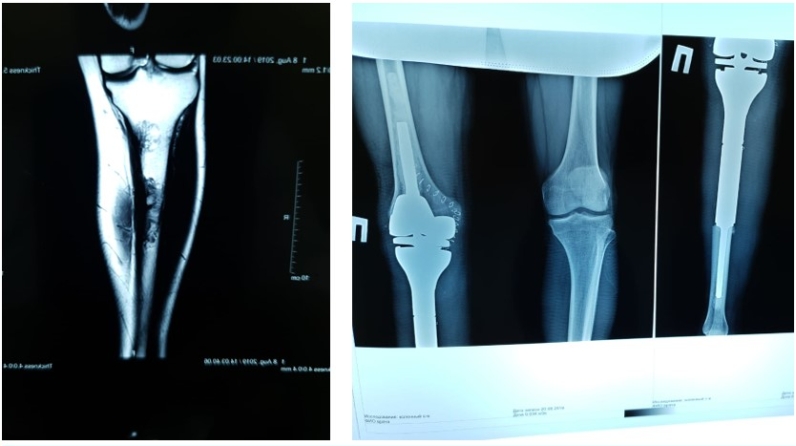

Республика клиник онкология диспансерында Татарстан Республикасында беренче тапкыр эндопротез белән тез буынын реконструкцияләү белән зур балтыр сөягенең шешенә югары технологияле оператив тыкшыну башкарылды.